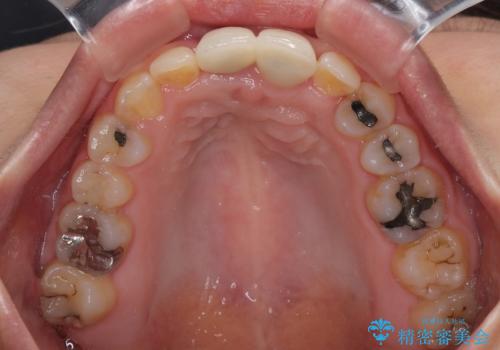

- 前歯のデコボコと、着色が著しい保険診療の前歯クラウンを気にして来院された患者様です。

左上の犬歯が埋伏しており、CT画像より萌出は困難と判断されたため、残存している歯にて歯列と咬合を整えることとしました。

前歯のクラウンは変色が顕著なため、矯正治療後にオールセラミッククラウンによる補綴治療を行うこととしました。